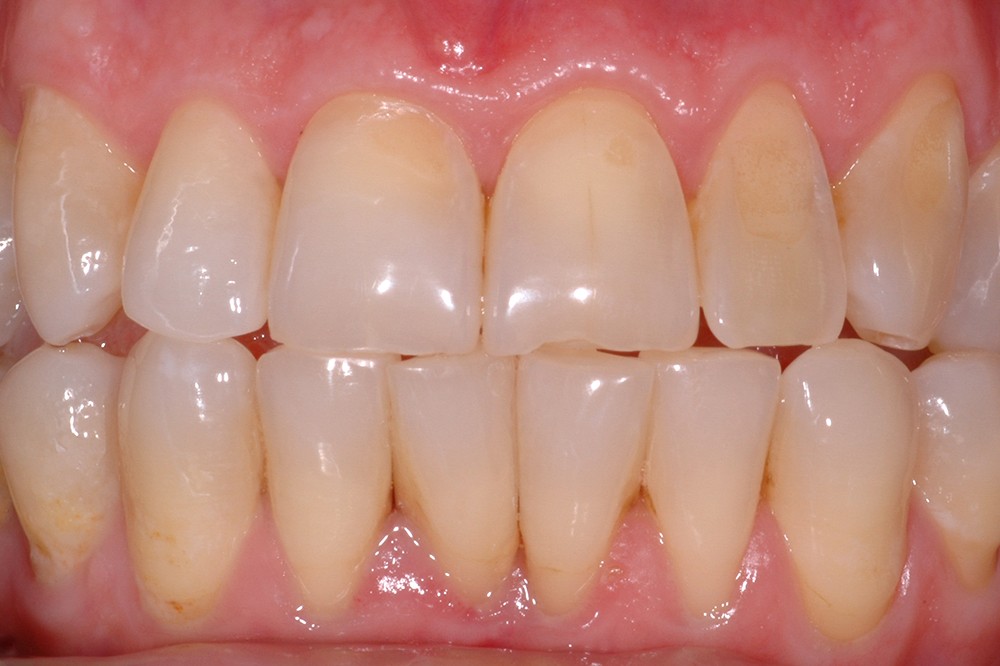

L’érosion survient lorsqu’une attaque chimique (solution acide, chélatant) rompt les liaisons intermoléculaires des tissus dentaires, potentialisant les différents autres modes d’usure mécanique (attrition, abrasion, abfraction) (fig. 5). L’aspect clinique des lésions érosives est polymorphe, mais, d’une manière générale, les surfaces sont lisses, en forme de cupules sur les sommets cuspidiens (fig. 6), de couleur satinée à terne. Les restaurations non affectées par l’environnement corrosif (amalgames, composites, alliages métalliques) surplombent généralement les surfaces amélaires et dentinaires adjacentes, alors que la morphologie dentaire est affectée. Les faces vestibulaires (fig. 7) et palatines (fig. 8) peuvent également présenter des lésions plus ou moins importantes, selon l’origine et le temps d’application de la source acide qui peut être d’origine extrinsèque (sodas, aliments acides) ou intrinsèque (sucs gastriques).